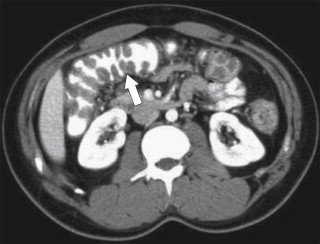

Ultrasound (US) sometimes shows a hypoechoic cystic mass with a thick wall, which has an echogenic outer layer and hypoechoic inner layer. On BE the cyst produces a mass effect of adjacent bowel and on CT appears as a nonenhancing mass, compressing or displacing the adjacent bowel, which may contain simple fluid, hemorrhage, or proteinaceous fluid ( Fig. 5-4 ). On MRI the enteric cysts are usually hyperintense on T2-weighted imaging, reflecting their cystic nature ( Fig. 5-5 ). Because many duplication cysts contain ectopic gastric mucosa, a Tc-99m pertechnetate radionuclide study can often show radionuclide uptake, which can also be observed within a Meckel diverticulum for the same reason.

Figure 5-4, Axial contrast-enhanced CT in a 46-year-old woman with a 4.5-cm homogeneous pararectal mass ( arrow ) caused by rectal enteric duplication.